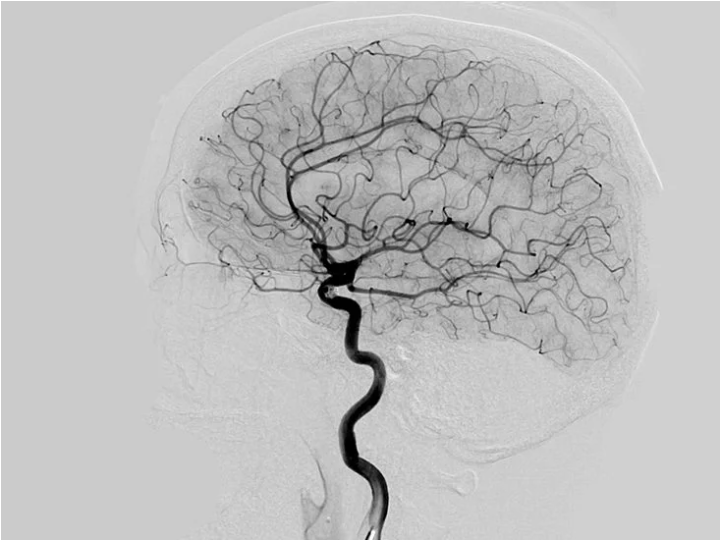

Як виконують церебральну ангіографію

Перед початком процедури Вам буде встановлено катетер у вену (на руці або передпліччі) для введення седативного препарату. Однак, деяким пацієнтам може знадобитися загальна анестезія.

Лікар зробить дуже маленький надріз у ділянці зап’ястя (рідше – в паховій ділянці). Під рентгенівським контролем катетер (довга тонка порожниста пластикова трубка) вводиться в кровоносну судину через крихітний отвір, зроблений голкою.

Потім через катетер вводять контрастну речовину. Коли контрастна речовина досягне кровоносних судин, буде зроблено кілька серій рентгенівських знімків. Коли процедуру буде завершено, лікар видалить катетер і накладе тиснучу пов’язку. Процедура зазвичай триває протягом 1-2 годин.